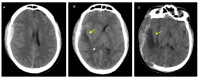

Cerebral edema is the abnormal accumulation of fluid in any of the tissue compartments of the cerebral parenchyma. It remains a significant challenge in neurotrauma care because it contributes to secondary brain injury, affecting prognosis. This review analyzes the recent literature, including foundational studies, to describe the mechanisms of distinct types of cerebral edema following traumatic brain injury (TBI). Emerging concepts, such as the role of the glymphatic system and heme-derived inflammasomes, offer new insights into new types of edemas, differentiated by pathogenesis and potential treatments. Recent advancements in understanding these molecular mechanisms can improve therapeutic strategies, facilitating a better approach in the era of precision and personalized medicine. Although there has been notable progress, a proposal to customize treatments for diverse types of edemas is necessary to improve outcomes following traumatic brain injury. In this review, we describe the current subtypes of post-traumatic brain edemas and link them to a specific management approach.